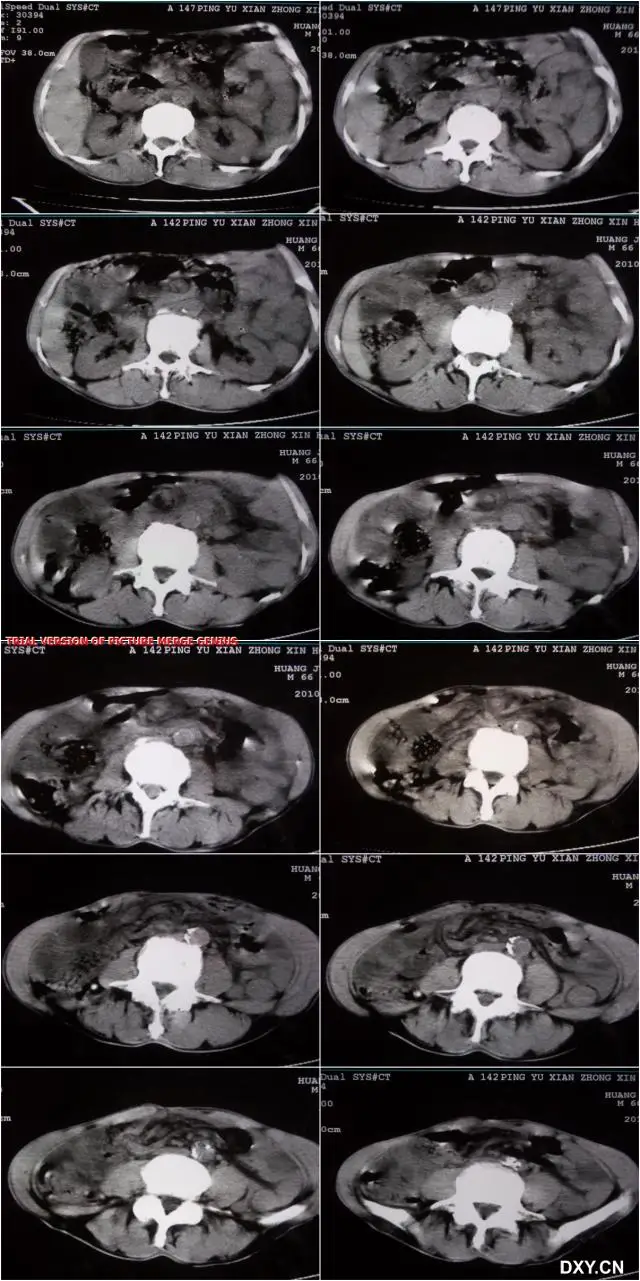

哎呀,说到这个肠套叠CT图,真是让人心惊胆战的!你知道吗,那种图一出来,医生们一个个都皱起了眉头,像是看到了什么不得了的大问题。我记得有一次,一个小朋友的家长拿着那张CT图来找我,脸上的表情比哭还难看。他们说,孩子肚子疼得厉害,做出来的CT图上,肠子就像是一条扭成了麻花的小蛇,真是让人看了心疼。

那图上的肠子,一层套一层,就像是玩偶里的小人儿,一个套一个,看得人眼花缭乱。医生说,这种情况要是不及时处理,孩子可是会有生命危险的。听到这话,家长的腿都软了,眼泪止不住地往下掉。我看着他们,心里也是五味杂陈,只能安慰说,医生们会尽全力救治的。